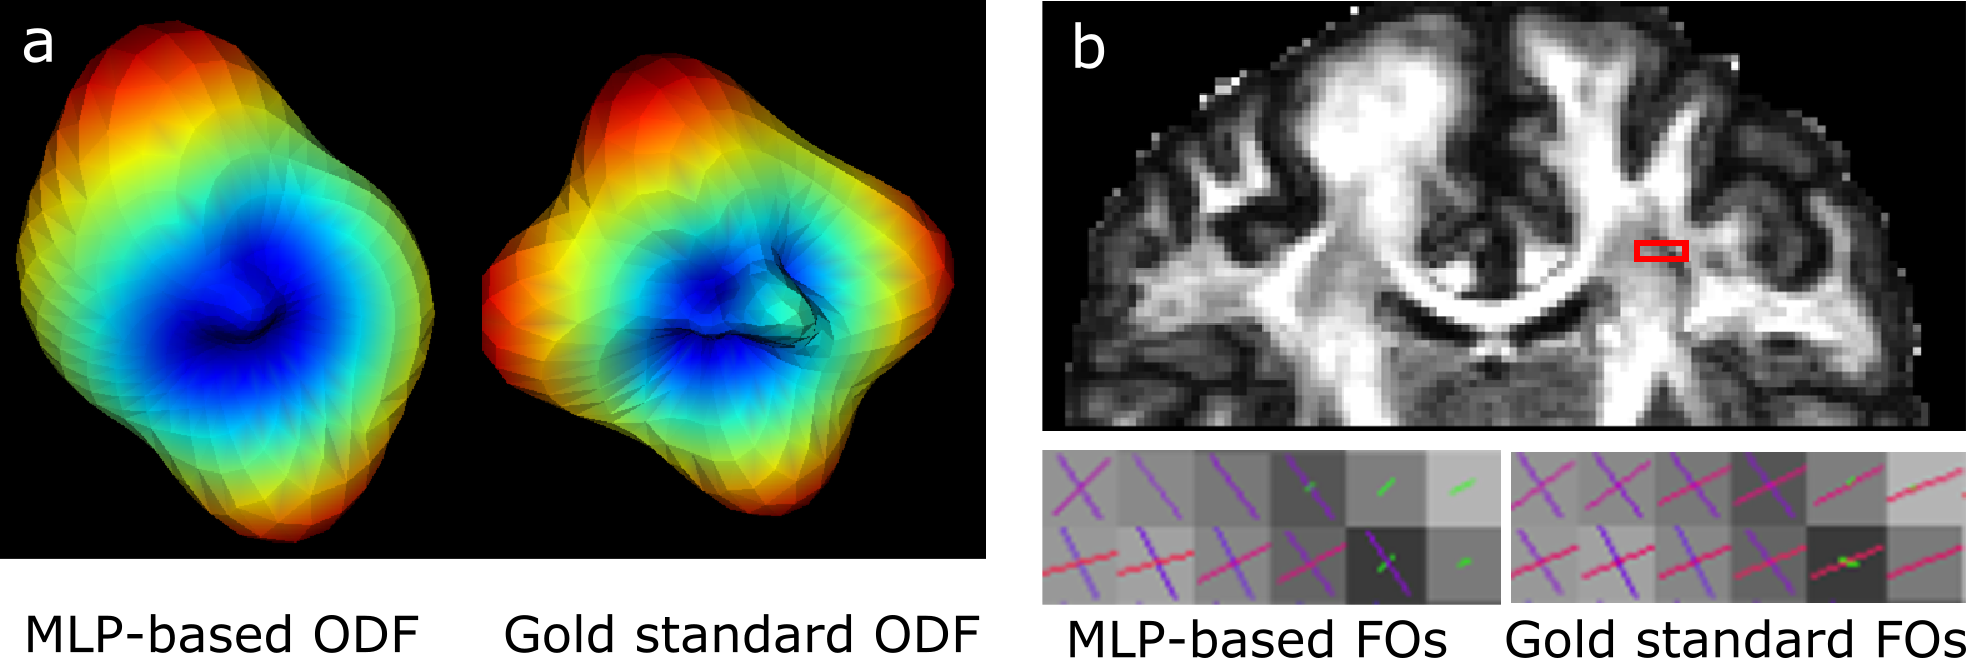

A straightforward strategy for EAP estimation would be to modify the MLP in [4] by giving vectors of coefficients at the output layer. However, typical loss functions, such as the mean squared error used in [4], cannot guarantee to properly capture the structure of the coefficients, which could lie in a non-Euclidean space. For example, we observed that the extraction of directional information of ODFs and FOs from the EAPs can be problematic with such a strategy. Fig. 1 gives an example of the ODF and FOs (overlaid on fractional anisotropy (FA)) extracted from the EAPs estimated using this simple strategy. The horizontal peak of the ODF is not preserved, and incorrect FO configurations with missing FOs can be observed. Even if a loss function that properly defines the difference of EAP coefficients can be discovered, computing its gradient in the training process can be nontrivial.

In this work, we propose a deep network structure described in Fig. 2(a), which uses the error of FOs as an auxiliary variable to regularize the computation of the EAP in the training phase. The network comprises two major components: 1) an MLP () that transforms the normalized diffusion signals to the basis coefficients that represent the EAP; and 2) the mapping to compute ODF values in sampled directions for the estimated EAP and the training EAP , followed by another MLP () that approximates the errors of FO estimation using the estimated ODF and the ODF computed from the training EAP. The approximated FO error is denoted by . Note that is known when the sampled directions are determined and is not trainable; and here we use 100 sampled directions. The second MLP is used to approximate the FO error because direct computation of the FO error from the ODF consists of complicated steps and the gradient of the error is difficult to compute during the training process. In this way, the gradient of the FO error can be easily computed for training the network. Like in [4], each MLP has three hidden layers. In each hidden layer, we use 500 units, which are more than the number used in [4], because we observed that EAP computation requires higher expressive power of the MLP. In the test phase, only the first component of the network is needed for EAP computation, as shown in Fig. 2(b).

Next, we evaluated the FOs extracted from the EAP. A qualitative comparison is made in Fig. 5, where we focus on a region where the corpus callosum (CC) and superior longitudinal fasciculus (SLF) cross. We can see that the LEAPE result resembles the gold standard, and LEAPE better resolves crossing FOs and produces smoother FOs than SHORE. The LEAPE FOs are even smoother than the gold standard in some cases. We also computed the average FO disagreement with the gold standard in the white matter for SHORE and LEAPE (see Fig. 4). Note that if the second MLP in LEAPE is not used for training, the FO errors range from to (not shown in Fig. 4), and for every subject the errors are higher () than those of SHORE or LEAPE. This indicates the benefit of adding the second MLP. Compared with SHORE, the mean and median of the disagreement of LEAPE are smaller. The difference of disagreement between SHORE and LEAPE is small. This is possibly because for the less complicated FO configurations (for example, noncrossing FOs), which occupy a large proportion of the white matter volume, both SHORE and LEAPE are able to produce good results with 60 diffusion gradients, and the difference like the one shown in Fig. 5 is present at regions with more complex FO configurations.